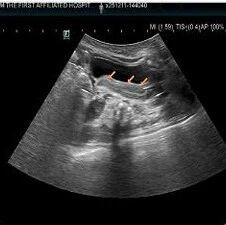

腹水细胞学三检纠偏,助诊潜伏间皮瘤:一例胸腹水细胞形态学在确诊恶性间皮瘤中的关键作用